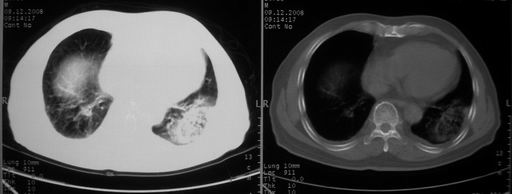

男,78岁,咳嗽、咳痰、发热入院,抗炎治疗一周后已退热,咳血似痰。

10月3日片: